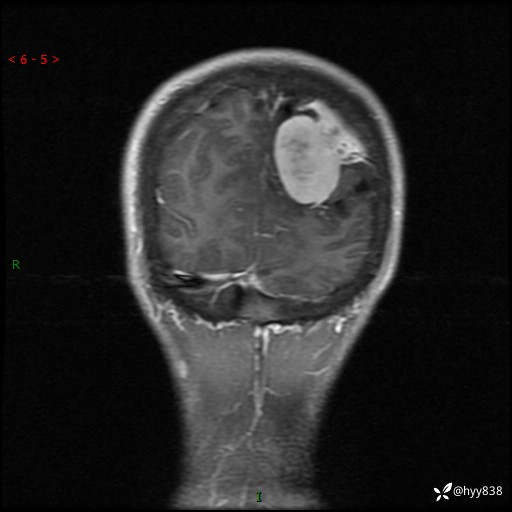

性别:男

年龄:21岁

简要病史:头痛伴呕吐半年,渐进性加重1月

颅脑MRI平扫+增强